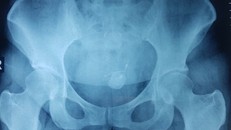

(Ngày Nay) - Nhập viện trong tình trạng tiểu buốt, đau bụng nữ bệnh nhân được bác sĩ kiểm tra và phát hiện chiếc vòng tránh thai nằm trong bàng quang đã hóa sỏi.

Bệnh nhân nữ 33 tuổi vào điều trị tại Bệnh viện đa khoa tỉnh Tuyên Quang sau khi xuất hiện triệu chứng tiểu buốt. Các bác sĩ sau đó xác định nguyên nhân gây bệnh là do vòng tránh thai "đi lạc" vào ổ bụng.